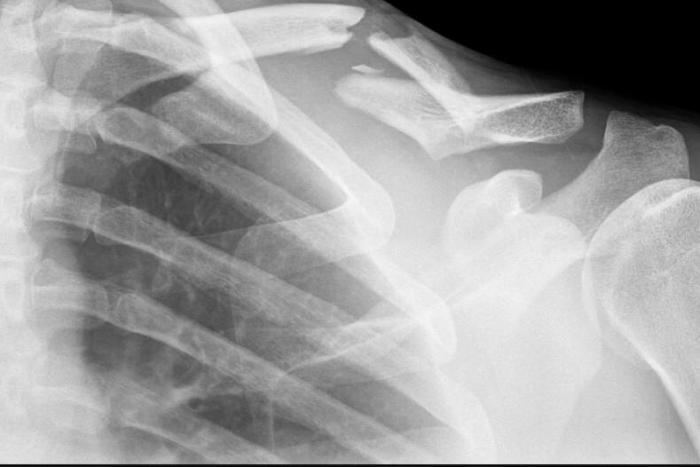

Uno de los motivos más frecuentes en las consultas de urgencias de los hospitales son las fracturas y otras patologías agudas traumatológicas. Las patologías agudas traumatológicas suponen un reto para cualquier facultativo que desarrolle su actividad en un servicio de urgencias; de hecho, en la mayoría de los países

desarrollados, los médicos implicados en la atención de las urgencias traumatológicas provienen de diferentes especialidades.

2.1. Hombro y brazo

2.1.3. Fractura de clavícula

2.1.7. Fractura de escápula